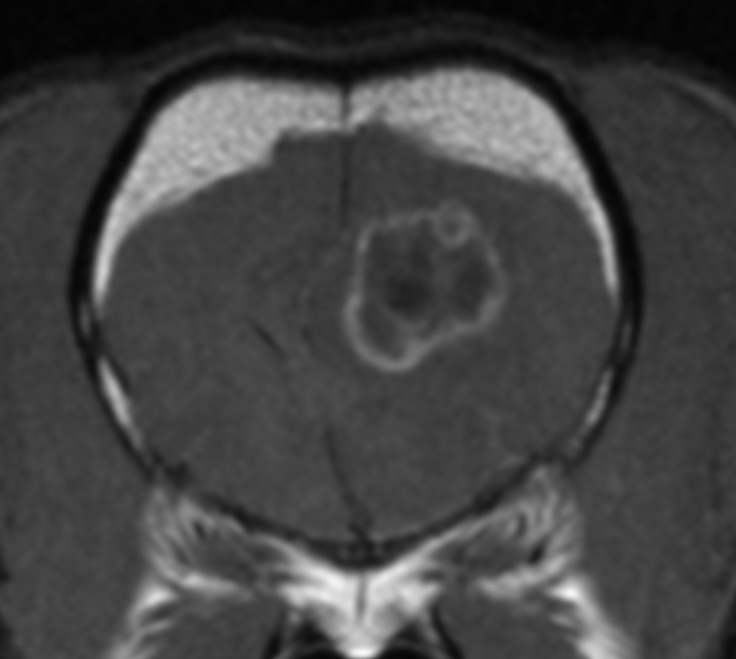

2例目

昨日KyotoAR(神志那先生)にて2例目の手術が行われました.今回もフレンチブル(5歳)さんです.

このまま少しずつ症例が増えていくと思います.